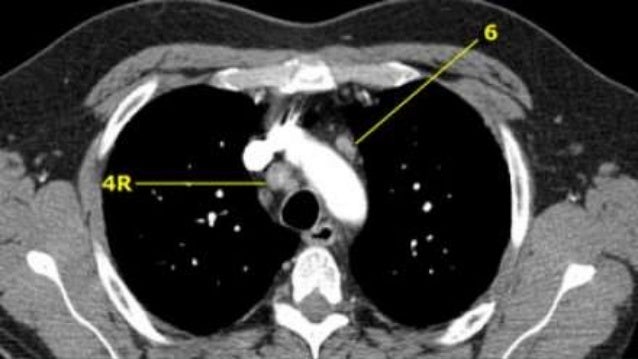

Radiological Anatomy Of Thoracic Lymph Nodes

lymph nodes thoracic radiological

Pitfalls In Ct Chest

pitfalls pericardial recesses